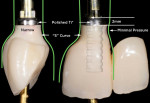

The appropriate gingival architecture must first be created by a provisional restoration that is properly designed to support, shape, and encourage development (Figure 2). After no less than 4 weeks of tissue maturation, the impression can be made. If the clinician does not act quickly during the impression procedure, it is inevitable that the gingiva will flatten before the impression sets (Figure 3). When this impression is poured up and the technician begins to plan the restoration, it will be apparent that the tissue will need to be reshaped on the cast. This process results in an abutment that is different in shape from that of the provisional, and this will result in tissue that will be different than was planned.

The goal of this discussion is to share a few techniques that will help clinicians make impressions for their technician that accurately capture the ideal gingival position. These procedures take place following maturation of the gingiva at the desired position using a provisional restoration. They are applicable for shaped gingiva, not for cases where the healing abutment has simply been removed for the impression (Figure 4).

There will be empty space surrounding the impression coping. Fill the space with dual-cure resin material (eg, Bisco Duo-Link™, BISCO, bisco.com), then polymerize. This resin will now fully support the gingiva as though the provisional were still in position. The entire process should take no more than 60 seconds. (Figure 5 through Figure 7). Verify fit radiographically. Make the definitive impression. (Figure 8).